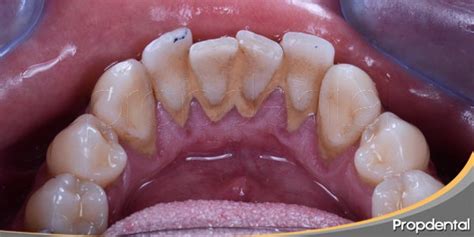

El sarro se distingue por su color, que puede ir de blanquecino a pardo. Además los problemas estéticos derivados de su aspecto desagradable, su presencia puede traer consecuencias negativas para la salud oral.

Existen dos tipos de sarro, el supragingival que es el que se puede observar a simple vista y el subgingival que no es visible y es el más perjudicial para las encías y los tejidos de soporte del diente (hueso).

¿Por qué se acumula sarro duro específicamente detrás de los dientes inferiores?

La anatomía oral explica por qué el sarro duro detrás de los dientes inferiores es tan común. Las glándulas sublinguales y submandibulares, ubicadas debajo de la lengua, secretan constantemente saliva rica en minerales directamente hacia la superficie lingual de los incisivos inferiores.

La superficie lingual de los dientes inferiores representa una de las zonas más desafiantes para mantener una higiene bucal adecuada. La posición de la lengua, la limitada visibilidad durante el cepillado y la dificultad para maniobrar el cepillo en esta área contribuyen a una limpieza incompleta.

Muchas personas concentran sus esfuerzos de higiene bucal en las superficies dentales más visibles, descuidando inadvertidamente las zonas posteriores y linguales.